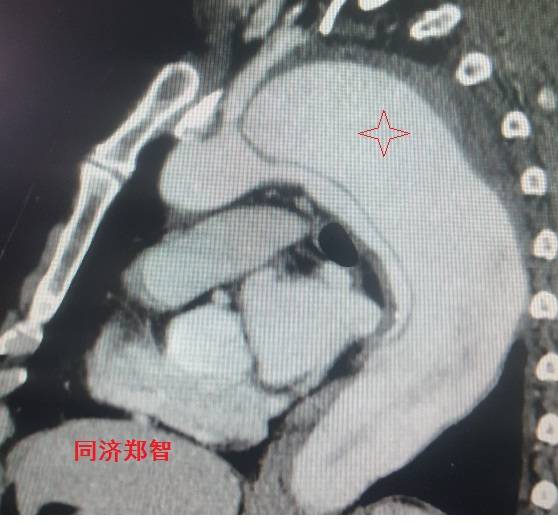

■ 病例二

胸部平扫CT提示升主动脉增宽(红色星形标记),CTA证实A型主动脉夹层伴升主动脉夹层动脉瘤形成。

图3